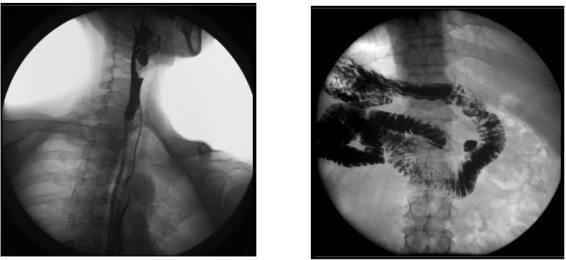

2、數(shù)字化胃腸功能:適用于胃腸道造影檢查,如食管造影、上消化道造影、全消化道造影等。

1) 消化內(nèi)科:可檢查直腸炎、結(jié)腸炎等;

臨床表現(xiàn)為腹痛、便秘等,癥狀為便血、黑便等。

2) 肛腸科:可應(yīng)用氣鋇雙重造影和排便造影(DFG)功能,可檢查大腸的細(xì)小病變,如小息肉、早期腫瘤、潰瘍等效果良好;可檢查肛管炎、恥骨直腸肌綜合癥、骶骨部畸胎瘤、直腸前突、直腸內(nèi)套疊、肛門直腸損傷和異物等檢查。

3、其他造影:適用于各種普通及特殊造影,如口服膽囊造影、靜脈膽道造影、T 管造影、逆行胰膽管造影(ERCP)、靜脈腎盂造影(IVP)、子宮輸卵管造影等。

1) 婦科:可檢查輸卵管堵塞、輸卵管粘連、輸卵管積水等慢性輸卵管疾病導(dǎo)致的不孕,可明確顯示輸卵管堵塞的部位、程度及性質(zhì),還可辨認(rèn)子宮內(nèi)膜情況,輸卵管和盆腔的結(jié)核病變情況;

2) 肝膽外科:膽管手術(shù)后,切開膽總管植入 T 管引流,起支撐作用,防止術(shù)后膽總管狹窄,術(shù)后應(yīng)用胃腸機進行膽管造影(T 管造影),檢查膽道內(nèi)有無殘留結(jié)石及異物,是否通暢無阻, 對手術(shù)進行評估;